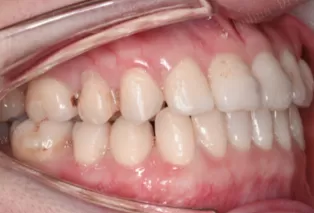

Photos intra-orales